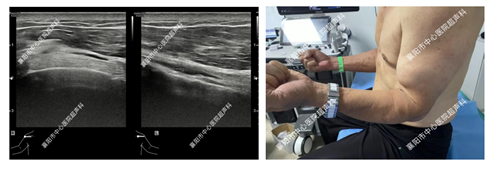

1、肌腱损伤的评估

(图中为玻璃划伤所致的手指肌腱断裂)

(图中为肱二头肌长头腱断裂)